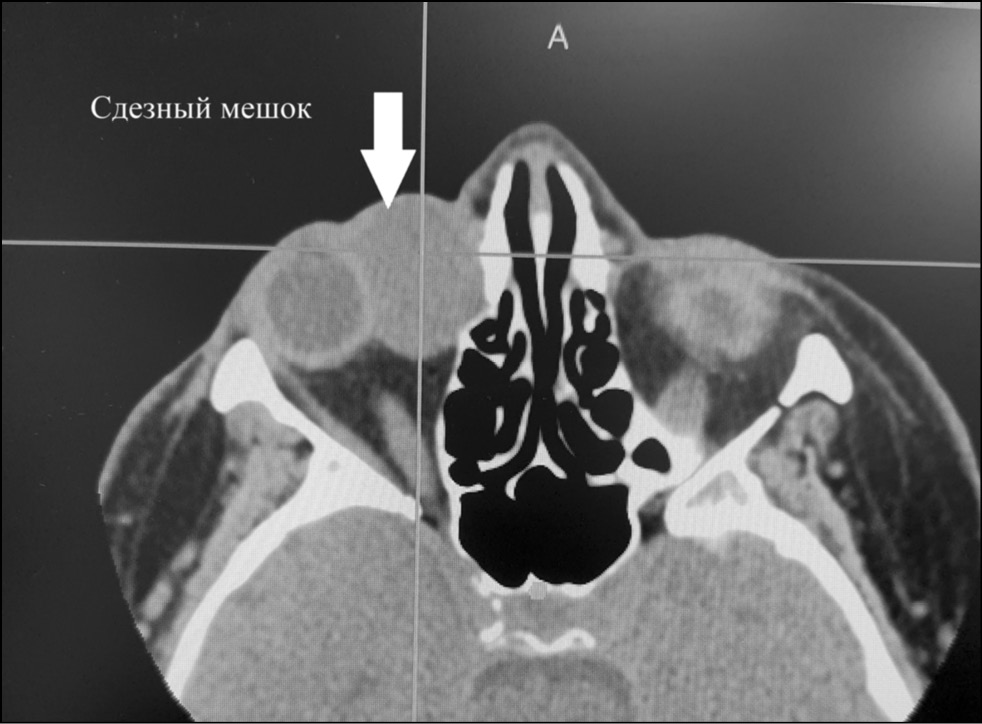

По результатам компьютерной томографии орбит, выполненной в трёх проекциях с шагом 1,5 мм, в области нижне-внутреннего угла переднего и среднего отделов правой орбиты, определяется образование овальной формы с чёткими контурами размерами 28,9 х 22,6 х 26,2 мм (рис. 2).

Рис. 2. Срез на компьютерной томограмме орбиты в аксиальной плоскости в проекции слёзного мешка.

Правое глазное яблоко смещено кнаружи и кверху, деформировано в проекции прилегания вышеописанного образования, расположенного вдоль медиального отдела глаза на всём его протяжении и превышающий объём глазного яблока в 1,5 раза.